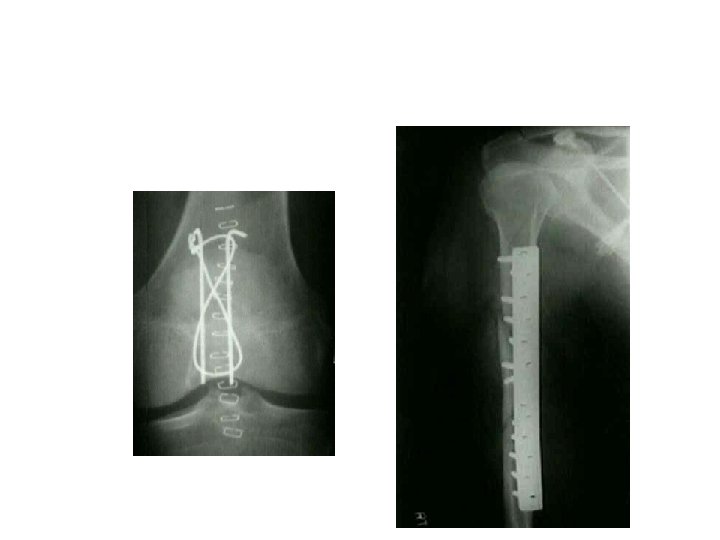

Open reduction 1 -displaced intra articular indications 2 -unstable Fr 3 -avulsion Fr 4

Open reduction 1 -displaced intra articular indications 2 -unstable Fr 3 -avulsion Fr 4 -Displaced pathologic Fr 5 - only operation indication 6 -Salter 3, 4 7 -compartment syn. 8 -NONUNION

Difinitive 1 -DEBRIDMENT 2 -FRACTURE TREATMENT A-INTERNAL FIXATION B-EXTERNAL FIXATION 3 - SKIN